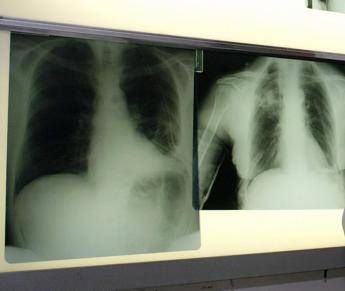

(Adnkronos) – Ogni anno circa 290mila casi di infezione respiratoria acuta negli adulti e 1.800 decessi. Sono i numeri registrati solo in Italia per il virus respiratorio sinciziale (Vrs o Rsv nella sigla inglese), che si presenta con sintomi simil-influenzali, ma può determinare complicanze respiratorie significative nei soggetti fragili come over 60, persone immunocompromesse e neonati. Un fenomeno sottovalutato e sottostimato, specialmente nella popolazione adulta e anziana: spesso, infatti, la malattia da Rsv non viene diagnosticata correttamente. La protezione dei soggetti fragili resta la priorità: in Italia si registrano infatti oltre 50mila ricoveri all'anno. Nel dettaglio si calcano circa 25mila ospedalizzazioni di bambini sotto i 5 anni di età legate alle complicanze come bronchiolite e polmoniti, e circa 26mila negli over 60. Sul fronte della prevenzione, sono oggi disponibili strumenti sicuri ed efficaci come la vaccinazione e l'immunoprofilassi; nonostante queste opportunità, però, l'Rsv non è ancora incluso nel Piano nazionale di prevenzione vaccinale (Pnpv). Di questi temi e della necessità di una informazione corretta e aggiornata sui rischi e sulle strategie di prevenzione a disposizione si è parlato al media tutorial 'Giornalismo scientifico e comunicazione biomedica: il caso della malattia infettiva da virus respiratorio sinciziale' promosso dal Master Sgp – La Scienza nella pratica giornalistica della Sapienza Università di Roma, con il contributo non condizionante di Pfizer, che oggi nella Capitale ha messo a confronto i giornalisti con gli esponenti del mondo medico-scientifico, specialisti in igiene, medicina preventiva e pediatria. La rilevanza per la salute pubblica dei virus respiratori risiede sia nell'impatto socio-sanitario legato alla loro larga diffusione, sia al potenziale pandemico espresso da alcuni ceppi di virus influenzali e coronavirus, ricorda una nota. "La maggior parte dei virus respiratori ha una spiccata tendenza stagionale – afferma Pier Luigi Lopalco, professore ordinario di Igiene, università del Salento – Nell'emisfero Nord del pianeta è nei mesi invernali che si verificano i picchi di infezioni da influenza, virus respiratorio sinciziale, Sars-CoV-2, metapneumovirus, rhinovirus e adenovirus, per citare i più frequentemente diagnosticati. La circolazione combinata di questi virus rende la stagione invernale particolarmente critica in termini di pressione sul sistema sanitario. Ancora oggi le informazioni che abbiamo sulla circolazione dei virus respiratori sono affette da una forte sottostima". Il sistema di sorveglianza, osserva Lopalco, "non è completamente efficiente nel rilevare i casi reali e ciò non consente di valutarne il reale impatto sociosanitario: a questo scopo – suggerisce l'esperto – sarebbe necessario impostare studi ad hoc che, laddove eseguiti, hanno mostrato che il danno individuale e sociale di queste infezioni va ben oltre il periodo della malattia acuta. Nei soggetti fragili e anziani, ad esempio, un periodo di ricovero dopo un'infezione respiratoria può scatenare una serie di complicanze e si associa spesso a una perdita consistente dell'autonomia". In Italia, dopo l'esperienza della pandemia da Covid-19, il sistema di sorveglianza dell'influenza Influnet si è ampliato diventando RespiVirNet, con l'obiettivo di migliorare le conoscenze su altri virus respiratori come l'Rsv che si possono prevenire con la vaccinazione. "La sorveglianza consente di misurare il reale carico di malattia, supporta la programmazione sanitaria e l'allocazione delle risorse, guida le decisioni sulle strategie preventive e aumenta la consapevolezza del carico di malattia – evidenzia Caterina Rizzo, professoressa ordinaria di Igiene e medicina preventiva, università di Pisa – Comprendere e comunicare il peso dell'Rsv a tutti gli attori coinvolti è essenziale per rafforzare la prevenzione, ridurre la sottostima e tutelare le fasce più vulnerabili della popolazione". Il virus respiratorio sinciziale colpisce in modo diverso nelle differenti fasce d'età. L'Rsv "è un virus ubiquitario che colpisce praticamente tutti i bambini entro i 2 anni di vita, con possibili reinfezioni nel corso della prima infanzia e financo in età adulta – illustra Paolo Manzoni, professore associato di Pediatria e neonatologia, università di Torino – Se nei soggetti oltre i 2 anni di età il virus causa spesso sintomi simil-influenzali, colpendo per lo più le vie aeree superiori, al contrario una percentuale importante di pazienti con età meno di 2 anni presenta coinvolgimento delle basse vie aeree che può sfociare, nello specifico, nel quadro clinico classico conosciuto come bronchiolite e nelle sue complicanze sia immediate, sia a lungo termine". Oltre ai neonati prematuri e di età inferiore ai 6 mesi, le popolazioni a rischio di sviluppare una patologia respiratoria grave a seguito di Rsv sono le persone over 60 e quelle immunocompromesse o con patologie preesistenti come il diabete, le malattie cardiache e polmonari, nelle quali il virus può scendere alle vie respiratorie inferiori causando principalmente polmonite. A partire dal 2023 – prosegue la nota – nell'Unione europea sono stati resi disponibili vaccini contro l'Rsv indicati per proteggere sia i neonati fino ai 6 mesi, attraverso la vaccinazione della mamma (le donne in gravidanza possono vaccinarsi dalla 24esima alla 36esima settimana di gestazione), sia adulti e anziani (le società scientifiche raccomandano la vaccinazione per i soggetti a rischio di 60-74 anni e per le persone di età pari o superiore a 75 anni). L'efficacia della prevenzione nelle persone over 60 è stata evidenziata da diversi studi, tra cui una recente esperienza real world pubblicata sul 'New England Journal of Medicine', che ha valutato un primo impatto del vaccino nel prevenire i ricoveri: il bivalente ha ridotto da 0,66 a 0,11 gli eventi per mille persone/anno, con un'efficacia dell'83,3% (Ci 42,9-96,9). Per le forme più gravi (tratto respiratorio inferiore), l'efficacia è salita al 91,7%, superando ampiamente il criterio di successo prespecificato. "Numerosi Paesi hanno già emanato raccomandazioni per la vaccinazione contro l'Rsv in base all'età (≥60, 65 o 75 anni) o ai fattori di rischio. Anche molte società scientifiche hanno fortemente raccomandato questa vaccinazione – rimarca Sara Boccalini, professoressa associata di Igiene, università degli Studi di Firenze – In Italia il Board del Calendario vaccinale per la vita raccomanda l'uso del vaccino contro l'Rsv per tutti i soggetti di età superiore-uguale ai 75 anni e per i soggetti affetti da patologie croniche di età uguale o superiore ai 60 anni. Tuttavia – precisa – al momento la vaccinazione contro l'Rsv non è raccomandata in base all'attuale Pnpv 2023-2025. La speranza è che le istituzioni sanitarie italiane integrino quanto prima l'offerta del vaccino Rsv per la popolazione anziana e a soggetti a rischio per patologie nel calendario delle immunizzazioni offerte attivamente e gratuitamente alla popolazione". La sfida principale – concludono gli esperti – resta duplice: da un lato rafforzare la raccolta di dati epidemiologici solidi per comprendere con precisione la diffusione e l'impatto della malattia infettiva da virus respiratorio sinciziale; dall'altro integrare in modo equilibrato le strategie di prevenzione disponibili, tenendo conto di tutte le popolazioni fragili a rischio di complicanze. Un approccio basato sulle evidenze scientifiche potrà fornire un contributo concreto al dibattito pubblico e istituzionale, sostenendo scelte consapevoli e mirate nella tutela della salute collettiva.